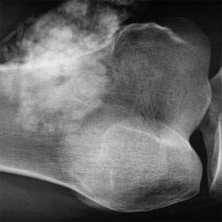

о Нейропатический акроостеолизис, может быть сильно выраженным и вовлекать большой объем костной ткани, помимо дистальных фаланг (20-70% случаев госпитализации)

о Остатки периферической кости могут иметь очень острый или тупой угол

о Нейрогенная артропатия лучезапястного или голеностопного сустава

о Периостит, остеомиелит (редко; 3-5% случаев госпитализации)